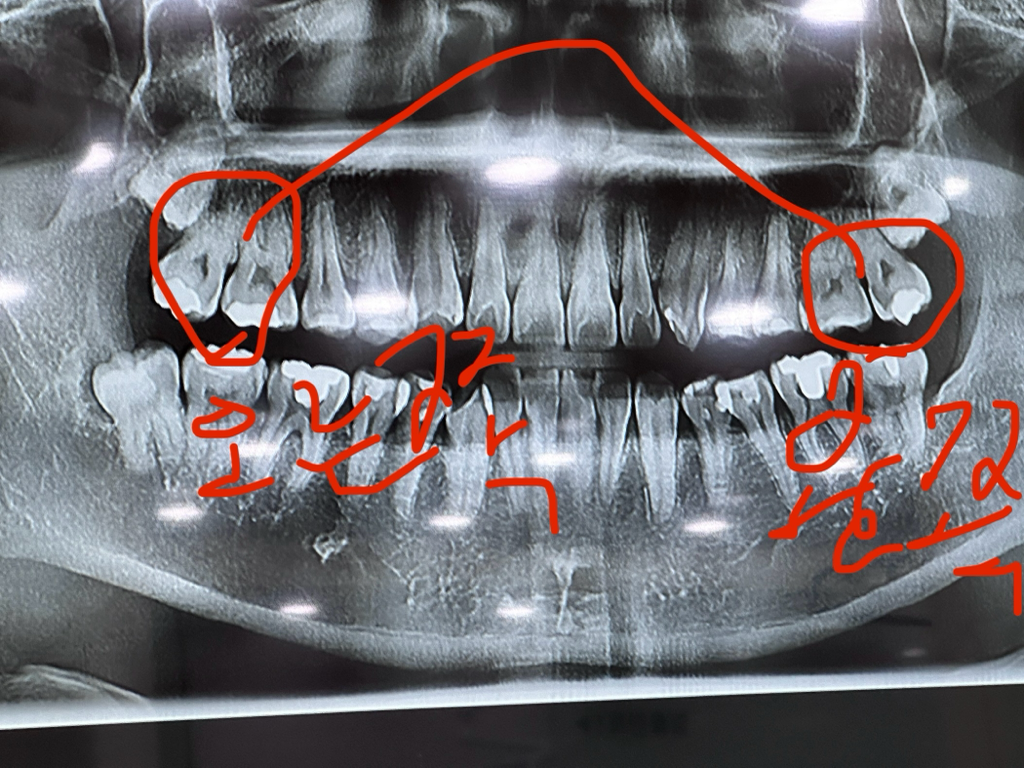

1주일 전 오른쪽 하단 사랑니 발치 때 찍은 사진입니다

엑스레이 사진으로 보면 양쪽위 어금니 사이에 충치가 있으신거 같습니다. 그래서 치실할때 불편하시고 물을 마시면 시린증상이 나타나는거 같으니 치료를 받으시는게 좋을것같습니다 .

왼쪽 위에 어금니의 경우에는 운전면에 충치가 있는 것으로 보입니다 충치가 있게 되면 빈 공간이 생기게 되어 해당 부위로 음식물이 끼어들어갈 수 있어요.

이런 충치는 충치를 치료해야만 해결되는 경우가 많습니다 온도 변화로 인해서 치아의 통증이 느껴지는 것은 충치가 신경을 감염시켜서 치수염이 발생되었기 때문에 가능성이 높습니다.

1-> 식편압입의 증상으로 보이고 계속 음식물이 끼면서 잇몸이 붓는 잇몸질환이 생긴 것 같습니다.

2-> 충치가 있으면 그럴 수 있습니다. 충치에 대한 검진(교익 방사선 사진) 필요합니다.

3-> 전반적으로 시리다면 잇몸이 좋지 않은 상태입니다. 왼쪽 위만 증상을 호소하셨는데 전반적으로 잇몸이 부어있거나 잇몸 높이가 낮아져 있을 수 있고(잇몸퇴축) 이런 경우 스케일링을 비롯하여 잇몸 치료를 들어가서 잇몸 관리를 하셔야 합니다.